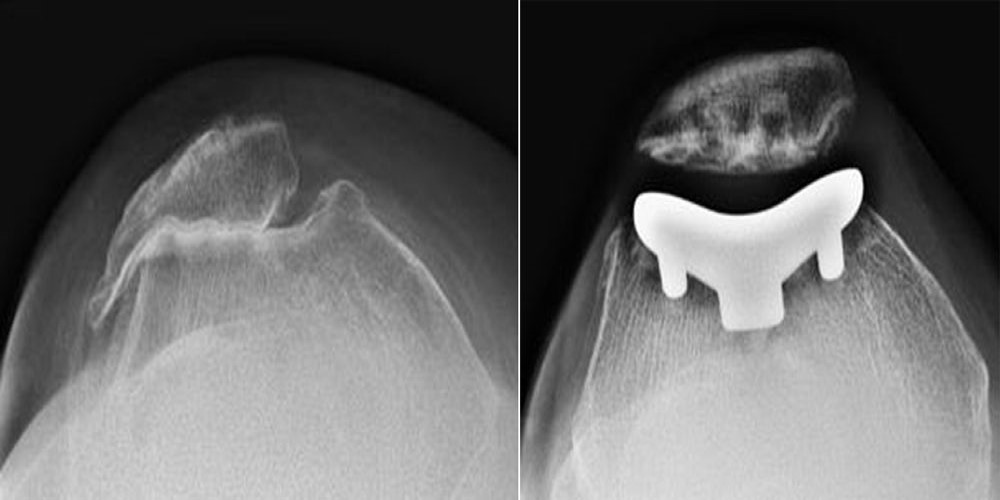

X Ray Knee Joint Lateral Views Showing A Preoperative And B Download Scientific Diagram